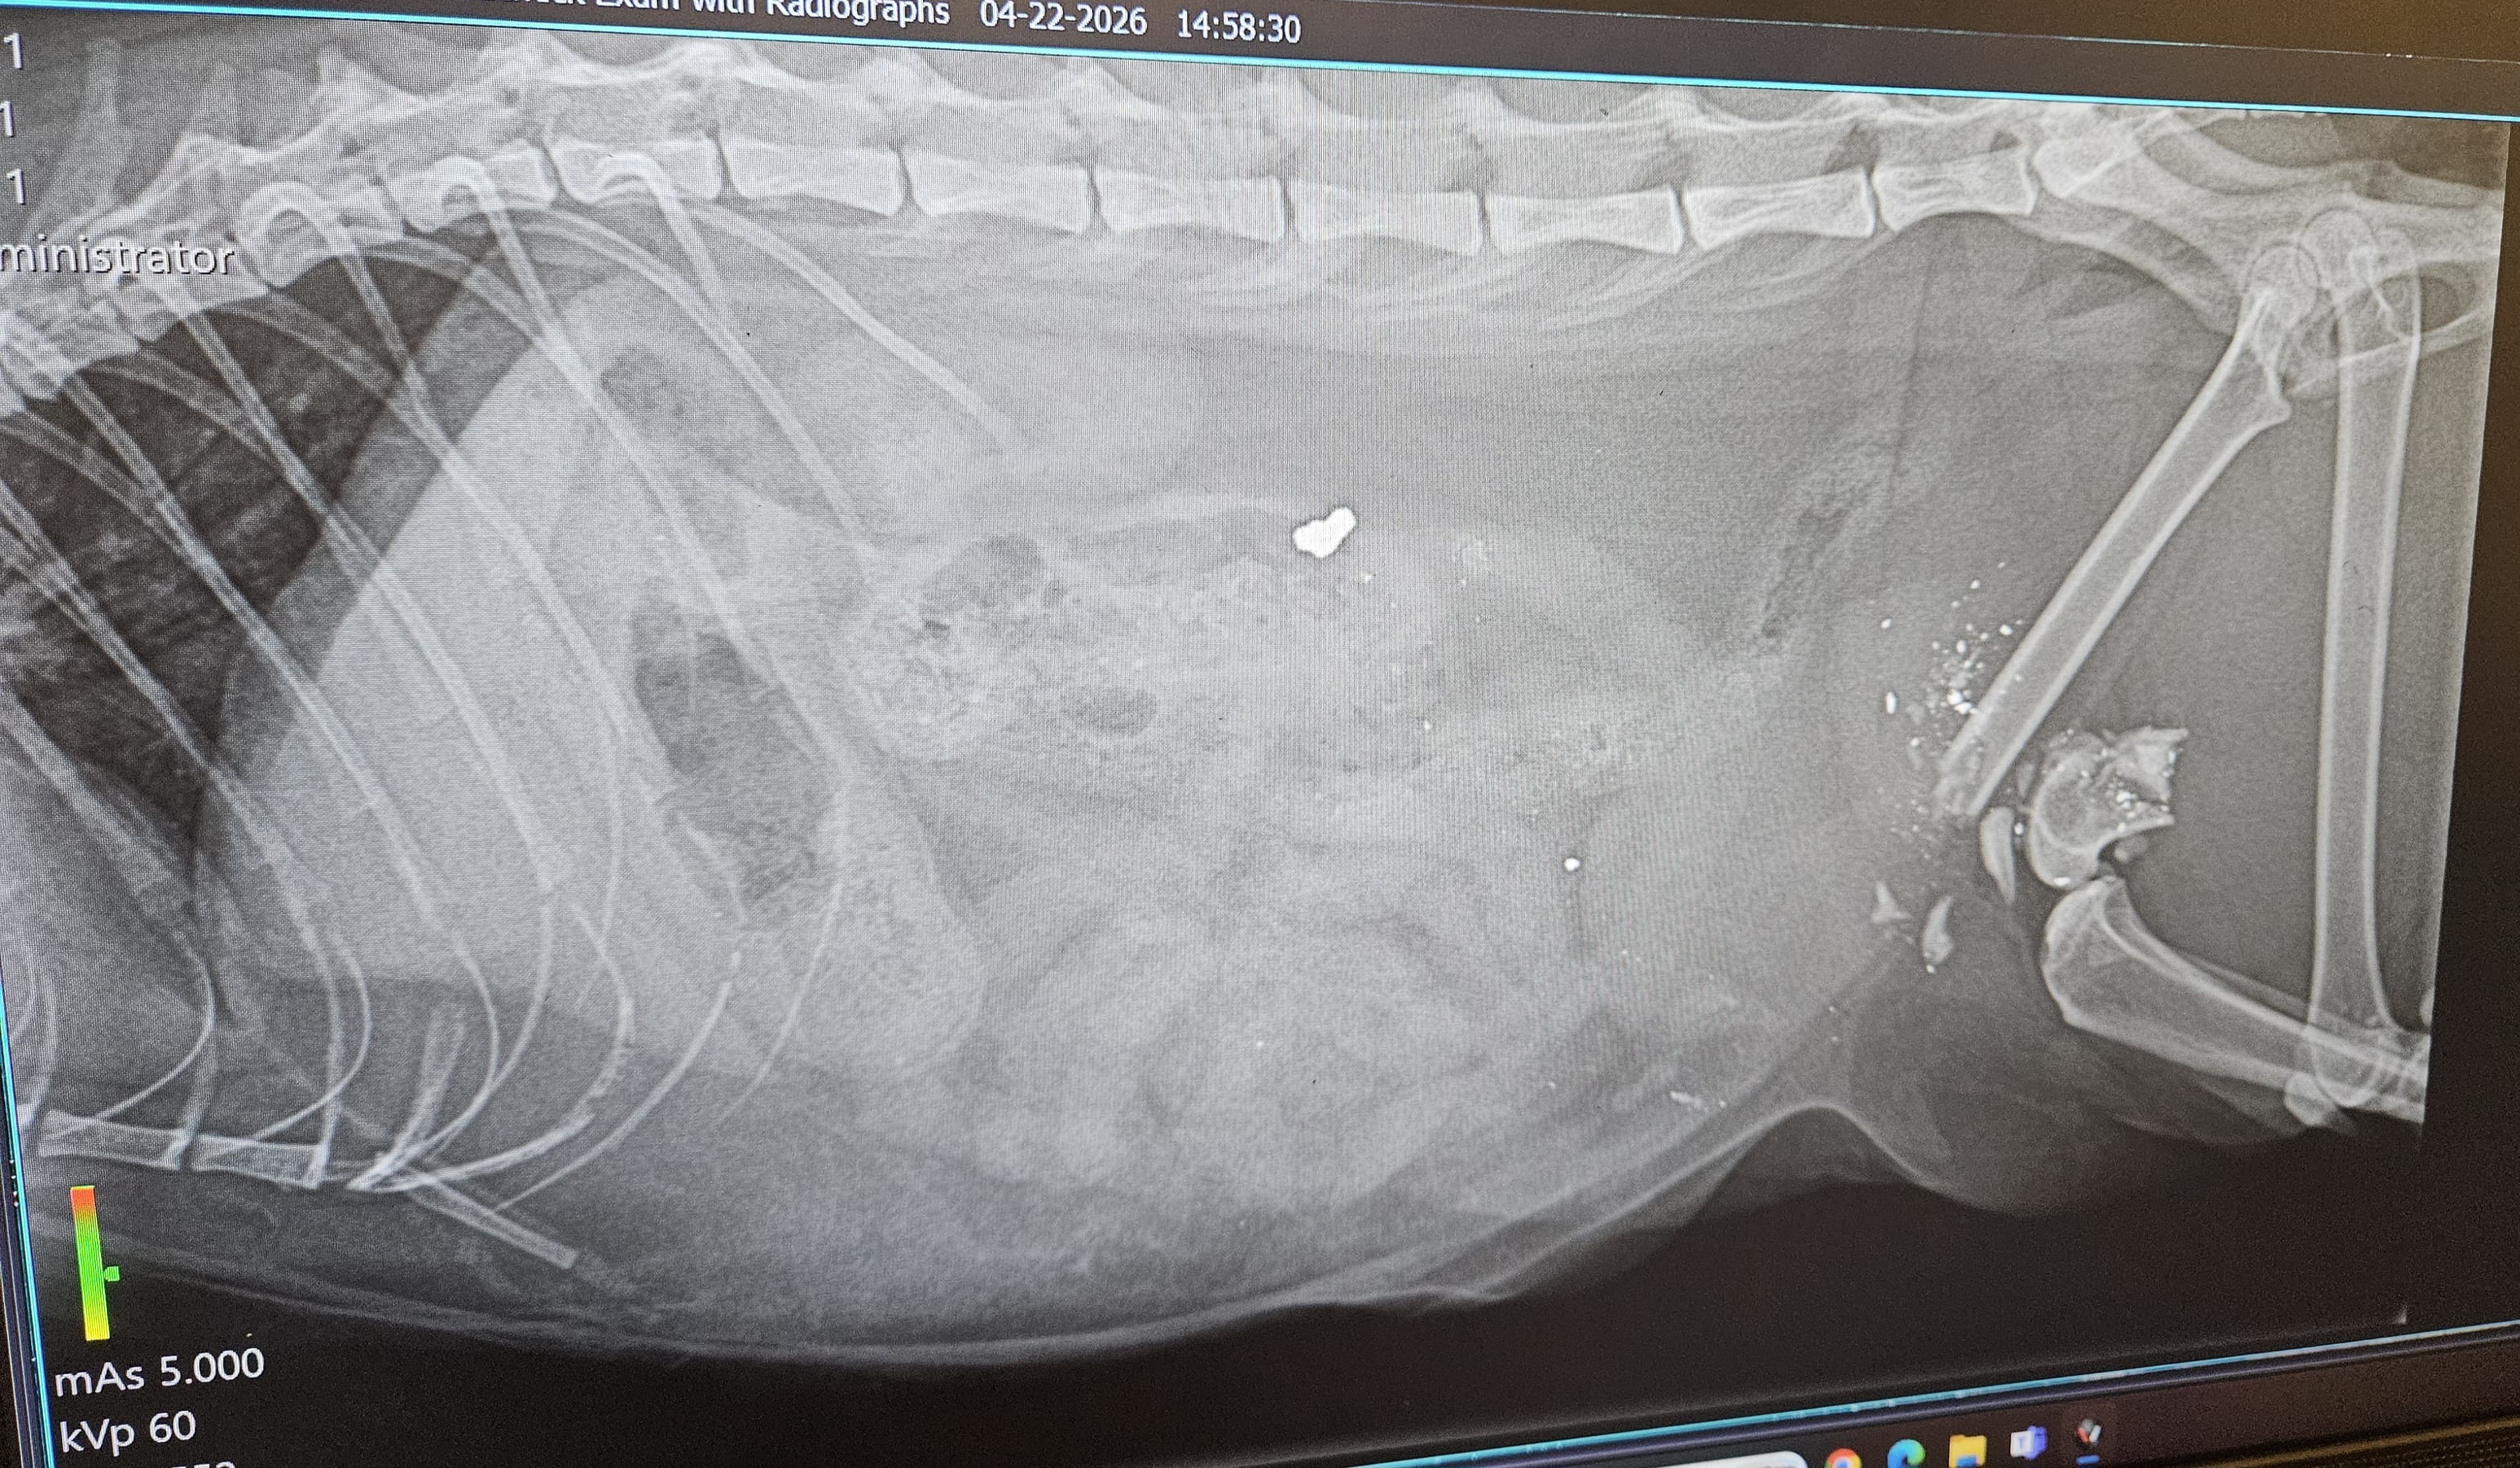

On April 20th Kiki was shot by one of our neighbors. I heard her meowing in pain and found her bleeding and with a shattered leg.

The vet says that Kiki needs surgery to repair her leg, along with several follow-up appointments to ensure she heals properly. It all is going to cost around 3400-3800 dollars. We simply cannot afford this and we desperately need your help.